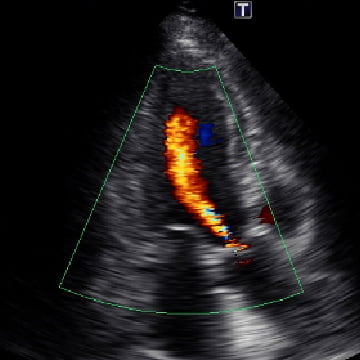

CT下肢動脈造影

狭窄